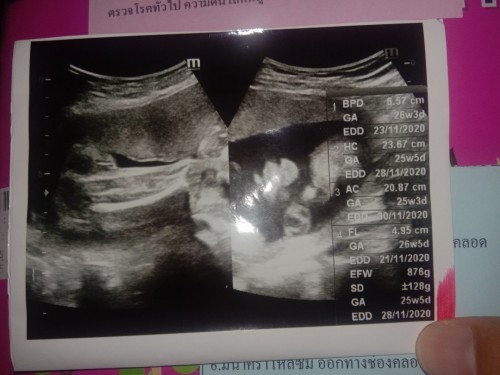

25วีค กลับหัวแล้ว เร็วไปมั้ยลูก😅 น้ำนมก็ซึมไม่หยุดเลย ซึมออกทุกวัน กลัวจะไม่ถึง9เดือนเด้

กลับท่าหัวเฉยๆค่ะแม่ ยังไม่ใช่กลับลงเชิงกราน ไม่ต้องกังวลค่ะ